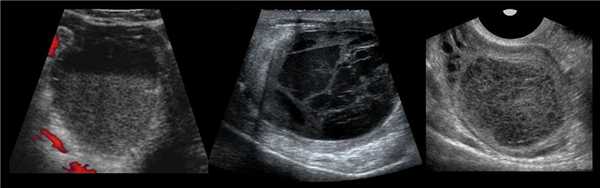

- Ультразвуковое исследование. На УЗИ геморрагическая киста выглядит как однокамерное образование с гиперэхогенными включениями.

- Допплерометрия. Кровоток внутри не определяется. При геморрагическом образовании желтого тела при обследовании видно «огненное кольцо» - характерный кровоток вокруг кисты.

Важным методом исследования является гинекологическое УЗИ (трансабдоминальным и трансвагинальным датчиками), а также допплерография яичника для исследования особенностей кровообращения в органе.